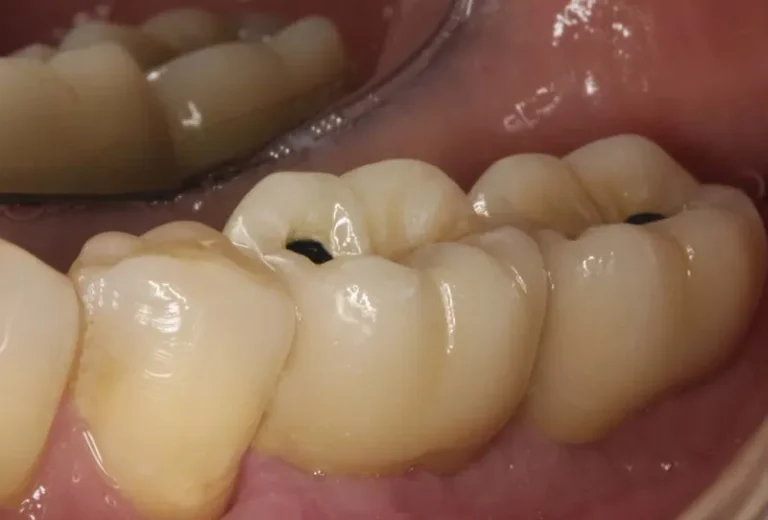

Los implantes dentales y los dientes naturales presentan características únicas que los diferencian tanto en estructura como en funcionamiento. Mientras los dientes naturales cuentan con ligamentos periodontales que proporcionan sensibilidad y capacidad de adaptación, los implantes se integran directamente al hueso mediante oseointegración. Esta distinción fundamental influye en aspectos como la sensibilidad a la temperatura,…